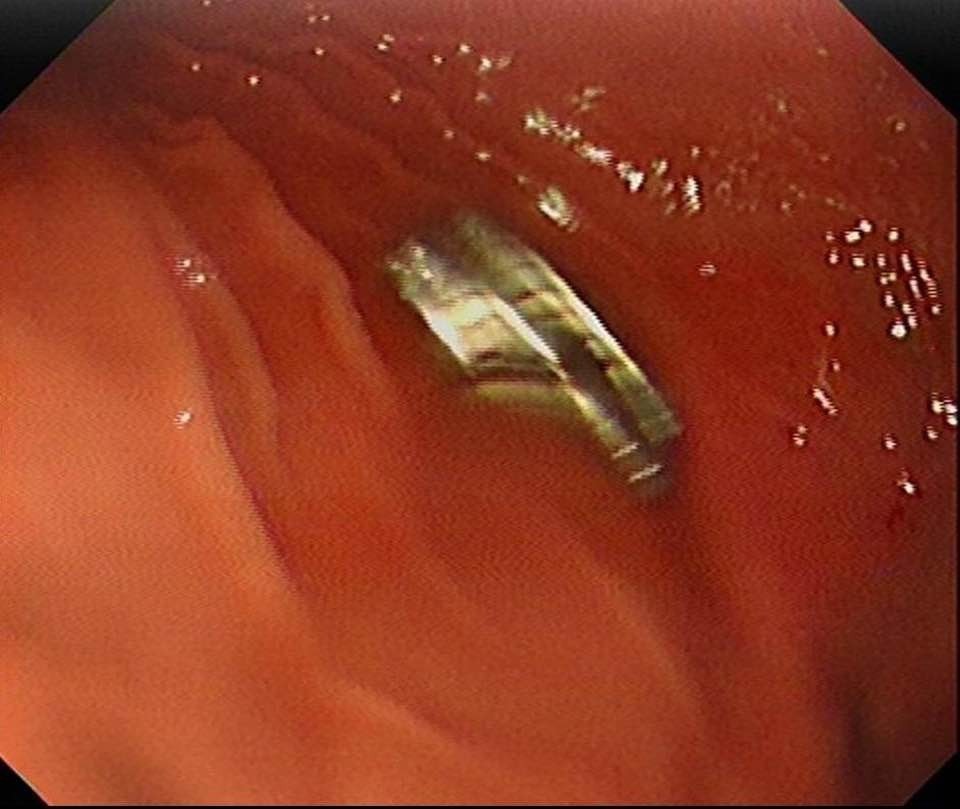

Fırat Üniversitesi Hastanesi’nde gerçekleştirilen müdahale ile çocuk, sağlık ekipleri tarafından tedavi altına alındı. Fırat Üniversitesi Tıp Fakültesi Çocuk Gastroenteroloji Hepatoloji ve Beslenme Bilim Dalı Başkanı Prof. Dr. Yaşar Doğan tarafından gerçekleştirilen endoskopik işlemle, çocuğun yemek borusuna yapışan 19 mıknatıs çıkarıldı.

Uzun süre yemek borusunda kalan mıknatısların, yemek borusu ve mide girişinde zedelenmeye yol açtığı tespit edildi. Yapılan tedavinin ardından hastanın sağlık durumunun iyi olduğu ve taburcu edildiği bildirildi.